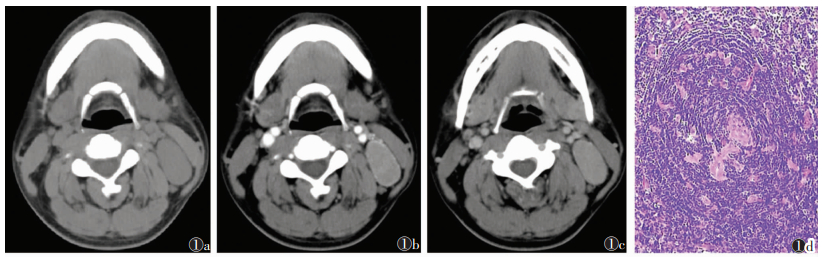

| 图 1 男,27岁,左侧颈部局限型透明血管型Castleman病(CD) 图1a CT平扫,示左侧颈动脉鞘旁(Ⅱ区)椭圆形肿块,边界清,CT值52 HU 图1b 动脉期呈均匀中度强化,CT值87 HU,边缘见血管影 图1c 静脉期呈持续均匀中度强化,CT值86 HU 图1d 病理示中心血管玻璃样变性,周围淋巴细胞呈同心圆状排列,并见小血管长入生发中心(HE×200) |

2 结果 2.1 CT表现10例中,局限型CD 8例,男5例,女3例,病理均为透明血管型,均为单发,其中1例术中见周围增大淋巴结3枚,病理上淋巴结反应性增生2枚,透明血管型1枚。10例中,位于颈部颈动脉鞘旁(Ⅱ区)2例、腹膜后肾脏前上方1例、前上纵隔(与主动脉宽基地相连)2例、后下纵区1例(9区)、右肺门旁1例、右侧盆腔入口腰大肌旁1例。CT平扫呈圆形、类圆形或椭圆形软组织肿块(图 1,2),7例密度均匀(图 1),1例密度不均、内见多发低密度区(图 2),2例伴斑点状、条状钙化,6例边界清晰,1例前上纵隔病灶与主动脉弓宽基地相连、分界欠清,1例右侧盆腔病灶与腰大肌分界欠清。病灶最大径3.3~8.5 cm(平均6.1 cm),2例颈动脉鞘旁及1例肺门旁病灶最大径均 < 5.0 cm,余5例最大径均>5.0 cm,且发生在腹盆腔者相对较大。增强扫描6例中,5例明显强化(图 2b,2c),1例中度强化(图 1b,1c)。4例均匀强化(图 1b,1c);2例不均匀强化(图 2b,2c),静脉期及延迟期病灶内部低密度灶显示明显。4例病灶周围见强化血管影(图 1b)。6例动脉期中度或明显强化、静脉期持续强化呈速升持续上升型或动脉期明显强化、静期强化略下降呈速升缓降型。

2.2 病理结果10例中,透明血管型9例,病理示增生的淋巴组织内散在分布大小不一的淋巴滤泡,滤泡生发中心小,滤泡内血管增生明显伴玻璃样变,滤泡中心淋巴细胞呈同心圆状排列,滤泡间区内见大量毛细血管增生,并见数量不等的浆细胞、嗜酸性粒细胞、组织细胞浸润(图 1d,2d)。浆细胞型1例,病理示滤泡生发中心正常或增大,滤泡间无明显毛细血管增生,有大量浆细胞浸润。